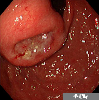

A case of advanced gastric cancer developed in the operated stomach,which showed a submucosal-like tumor appearance.

Malignant epithelial tumor/Undifferentiated carcinoma